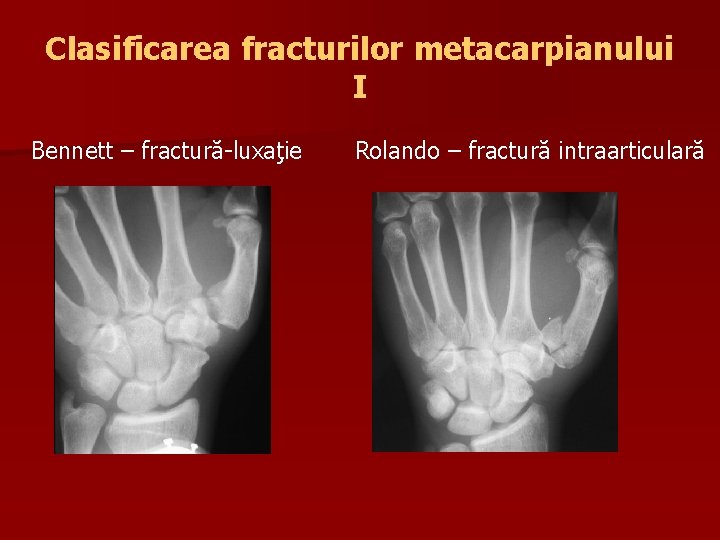

Clasificarea fracturilor metacarpianului I Bennett – fractură-luxaţie Rolando – fractură intraarticulară